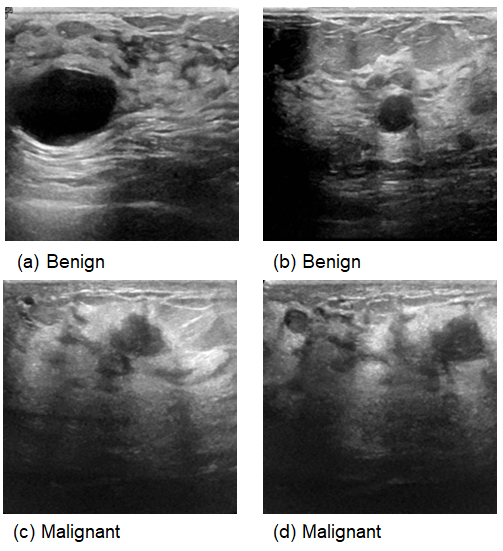

This comprehensive approach of utilizing datasets from multiple imaging modalities shown in Figure 1, Figure 2, Figure 3 and Figure 4 and summarized in Table 1, including mammography, ultrasound, MRI, and histopathological images, ensures robust model validation and enhances the system’s capacity to accurately classify benign and malignant findings. By leveraging these diverse datasets, we aim to develop a more generalizable and effective breast cancer classification system.

Figure 3. Samples from Ultrasound images.